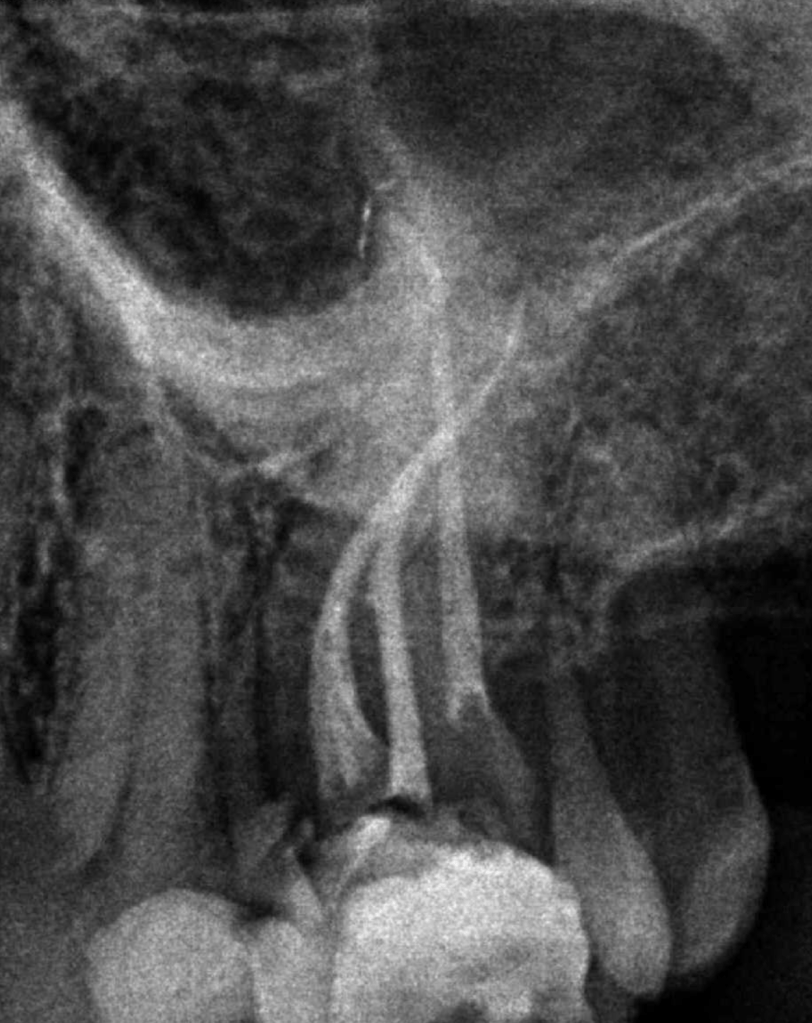

Bifurcación conducto palatino apical